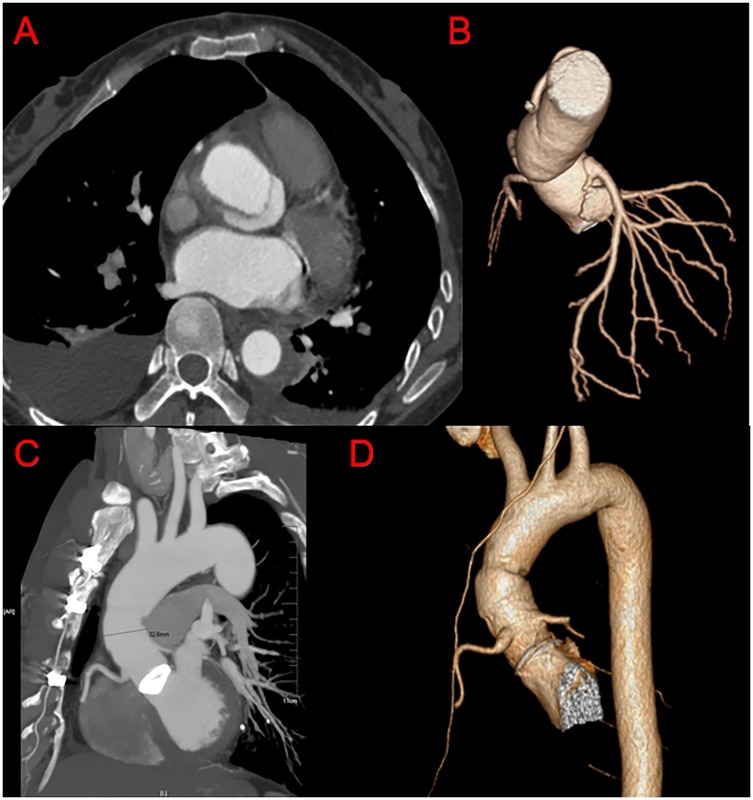

Background: Due to complications such as aortic root bleeding and high coronary tension with the conventional Bentall technique to treat aortic root aneurysms, new methods have been developed to enhance patient outcomes. This study aimed to describe a novel modification of the Bentall procedure for aortic root replacement and to report on its mid- and long-term follow-up outcomes. Methods: Patients diagnosed with aortic root aneurysm were enrolled in the study. The inclusion criteria included diameter of ascending aorta larger than 50 mm and the aortic valve with organic lesions. Data were collected including surgical time, aortic clamping time, cardiopulmonary bypass time, and pre-discharge computed tomography angiography findings. Results: Eighty-eight patients (nine with Marfan syndrome), including 69 men (78.4%) and 19 women (21.6%), underwent aortic root replacement using our new root reconstruction technique from 2011 to 2020 at our hospital. The patients’ mean age was 43.4 ± 11.7 years (range, 20–71 years). Of them, 35 (39.8%) had a Stanford type A aortic dissection (dissection group), while 53 (60.2%) had an aortic root aneurysm (aneurysm group). The patients’ in-hospital mortality rate was 2.3% (one case of multiple organ dysfunction syndrome, one case of arrhythmia). The mean aortic cross-clamp and cardiopulmonary bypass times were 120.9 ± 27.1 min and 159.2 ± 37.9 min, respectively. The follow-up rate was 94.2% (81/86) for a mean duration of 55 ± 23 months (range, 6–120 months). Follow-up mortality occurred in three cases (3.7%), including one death due to a traffic accident, one death due to cerebral hemorrhage, and one sudden death of unknown reasons. No patients required an aortic root re-operation during follow-up. The overall survival rate was 98.8%, 95.9%, and 95.9% after 48, 96, and 120 months, respectively. Conclusions: Our initial experience suggests that this technique is feasible and safe, with promising mid- and long-term outcomes in our series. These descriptive results justify further comparative studies to evaluate its role as a potential alternative for the treatment of aortic root aneurysms.